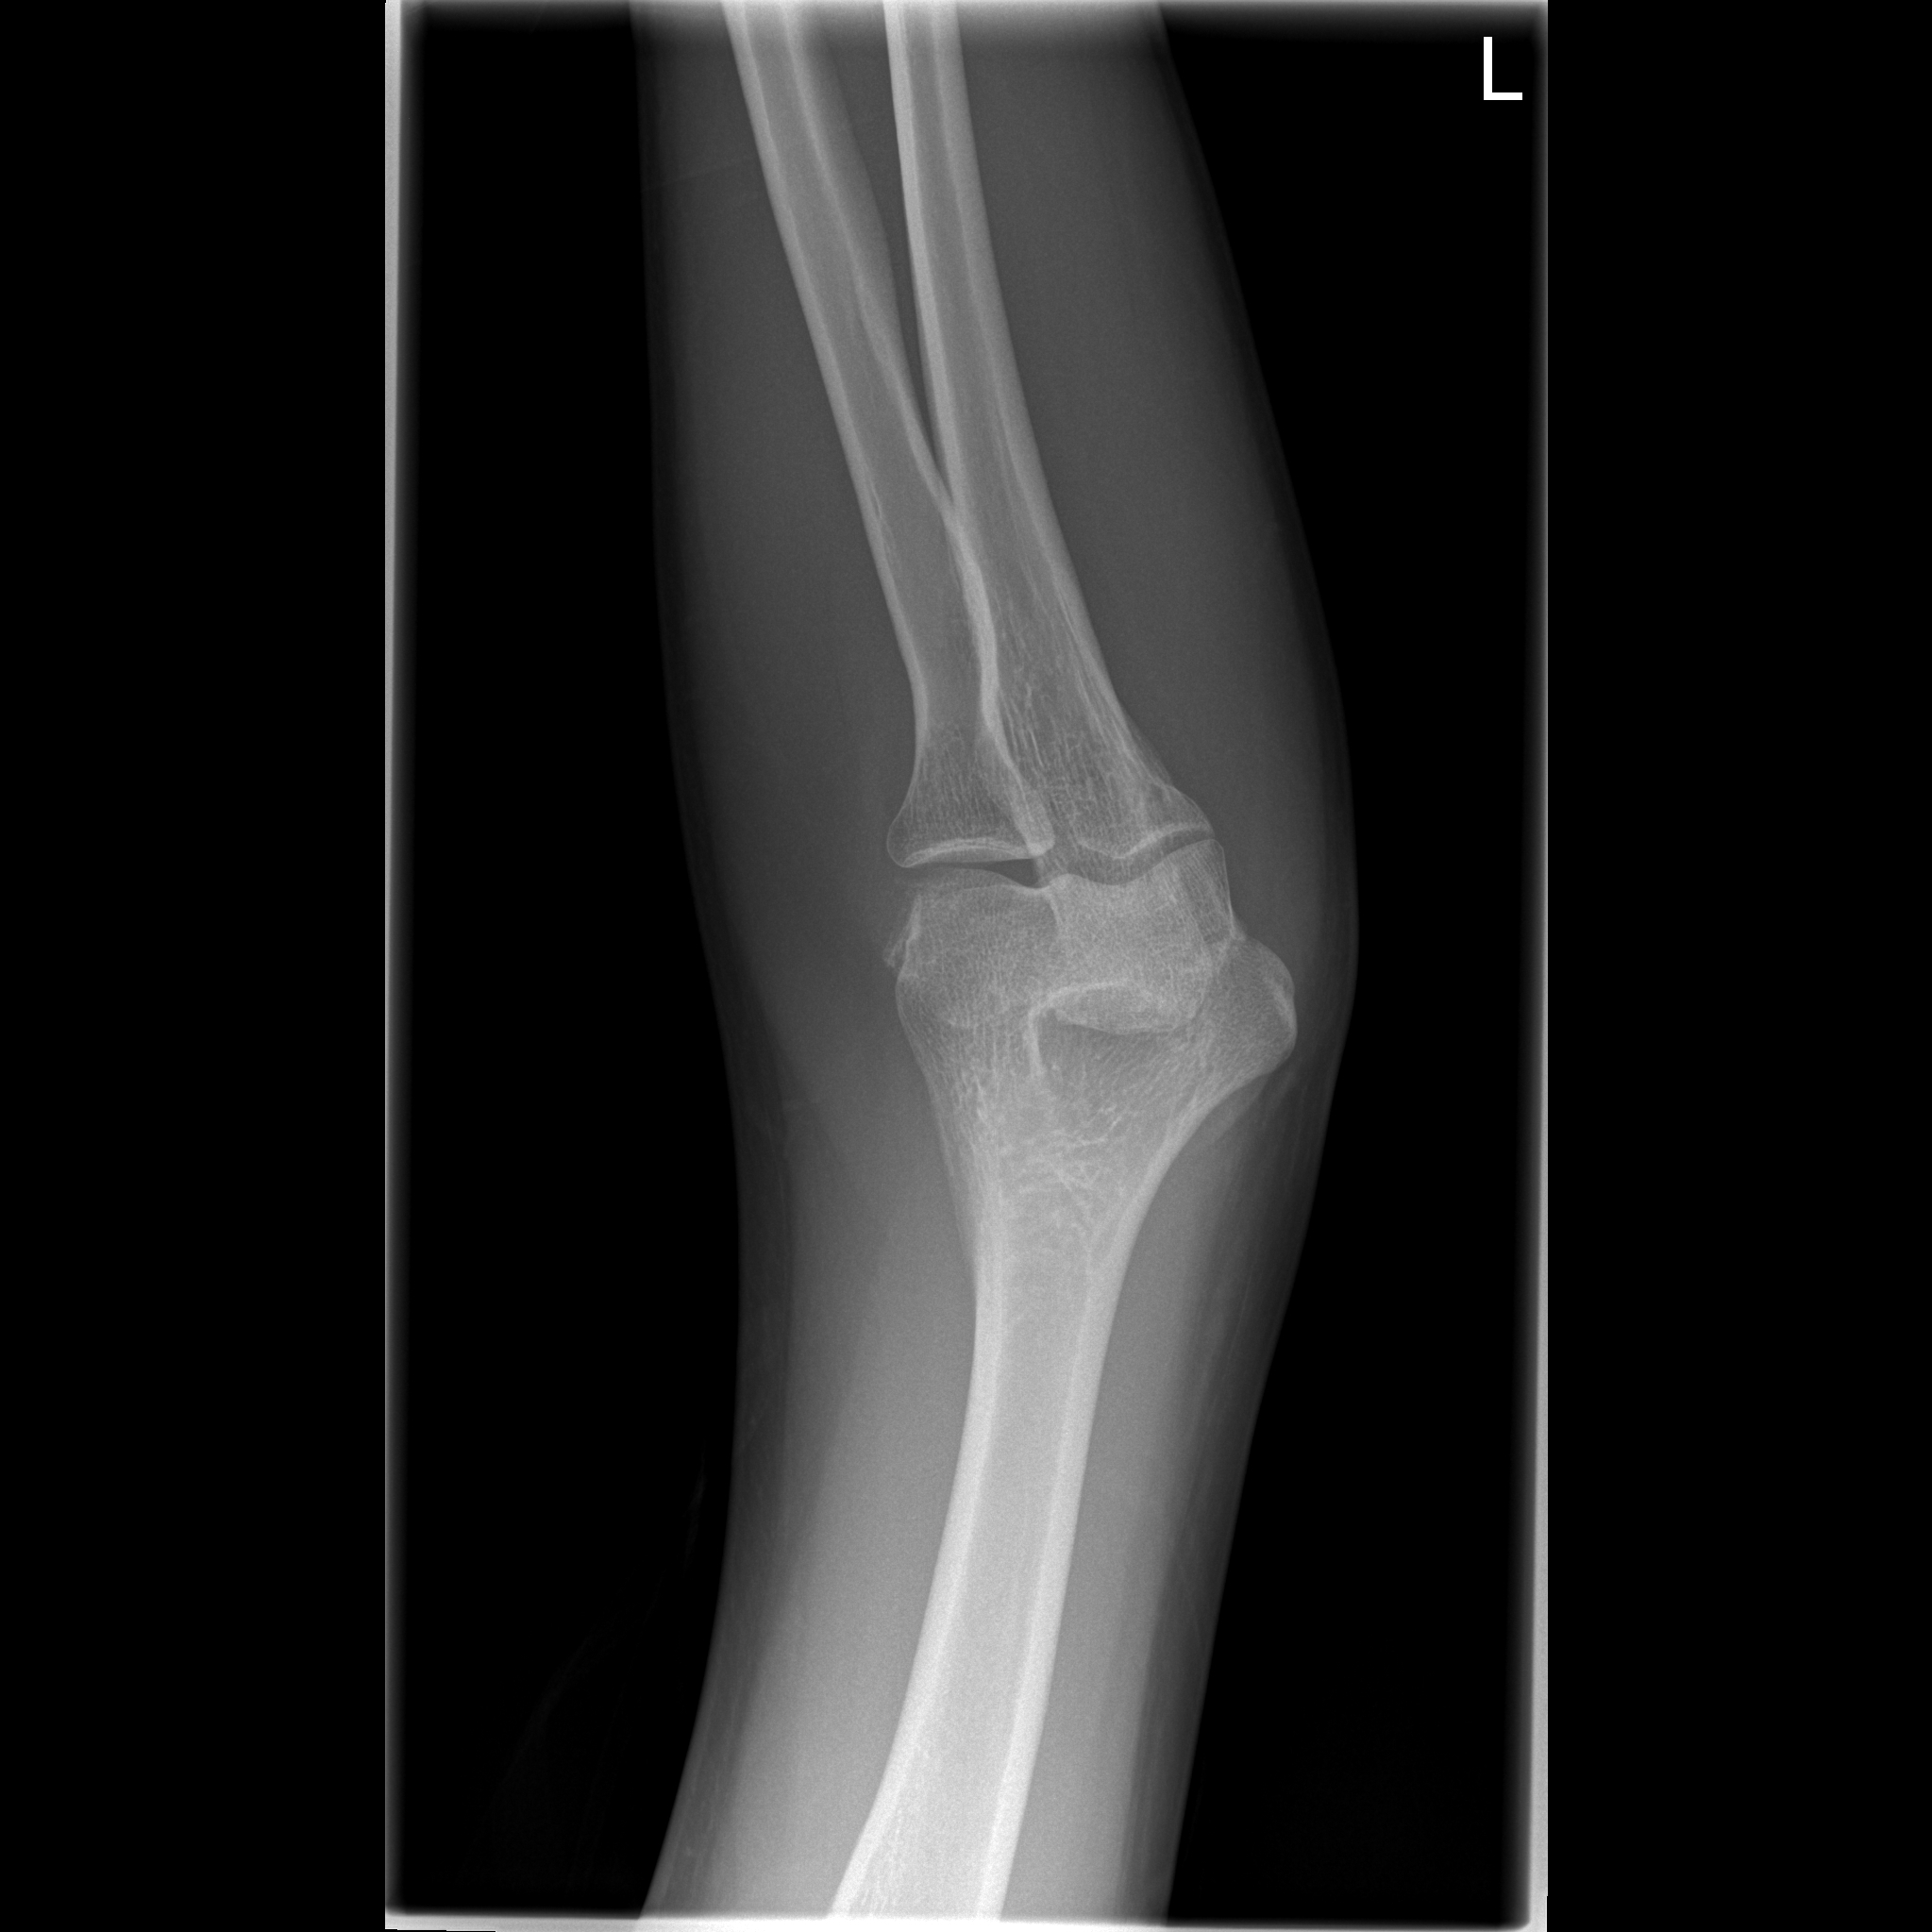

We will start explaining what a CT scan is. CT stands for Computed Tomography and is an imaging technology based on X-rays. X-rays are a type of light with very high energy. Most objects are translucent in this light, that is to say, they allow the light to pass although they might absorb part of it. Bones, for example, absorb more X-ray light than other tissues. For this reason, X-rays are used to take pictures of what is inside our body. If you have ever received an X-ray for a fractured bone, the doctor often will take two images, so that each of the two images show everything inside us from a different perspective. Certain features that may appear in the same spot in one of the images (for example a bone hiding behind a different bone), will be separated in the other one. With both these images, a physician may have a better understanding of what is happening than with a single one. If we increase the number of images we take, such as if we took three images instead of two, we could differentiate even better the spatial distribution of our insides. If we take this approach a step beyond and take an X-ray image from every possible angle in a 360 degree circle around the patient, then we would know perfectly the shape and location of every organ in our patient’s body. With all this information, it is possible to use a Computer (the C in CT) to transform this set of images into a single 3D image. This is the fundamental operation of a CT scan.